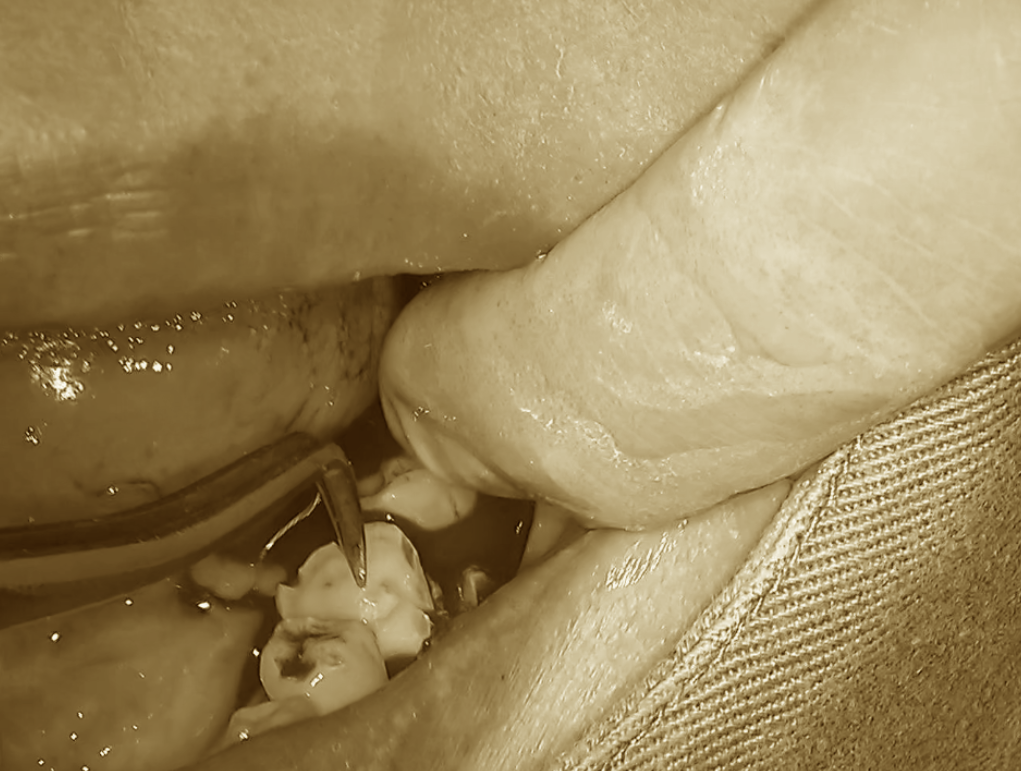

続いて、移植歯の抜去に移ります。

歯根に余計な力が加わらないよう、

鉗子を用いて丁寧に摘出していきます。

すでに移植床は完成しているため、

抜去した歯は速やかに移植部位へと移動させることができます。

ここで重要なのは、

いかに無駄な時間をかけずに移植まで進めるかです。

移植歯を挿入し、適合状態を確認した後、

今度は術後の安定性を考慮した処置を行います。

咬合による負担を避けるため、

歯冠部分を調整し、再度移植床へ戻します。

そのうえで、最も安定する位置を見極め、

最終的なポジションを決定します。